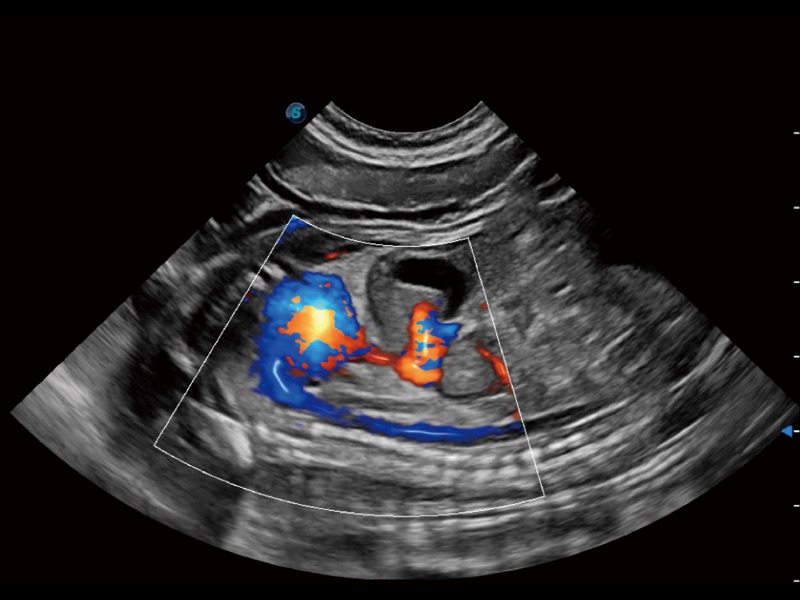

通過創(chuàng)新的 Matrix E自適應(yīng)濾波器和超長時間域算法,極大提升超低速微細血流的檢出能力,同時更精準地濾除軟組織和噪聲信號,為獸用醫(yī)生提供以往無法通過常規(guī)血流獲得的疾病診斷信息。

通過色彩血流和實時寬景相結(jié)合,可觀察到完整的靜脈或動脈的血流,方便醫(yī)生檢查。實時掃查過程中,如有任何操作失誤也可以很容易地進行回掃擦除,而不會中斷掃查。